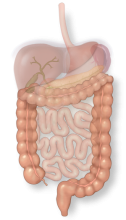

The colon is a large tube that stores feces and also contains helpful bacteria that breaks down food that has not yet been absorbed.